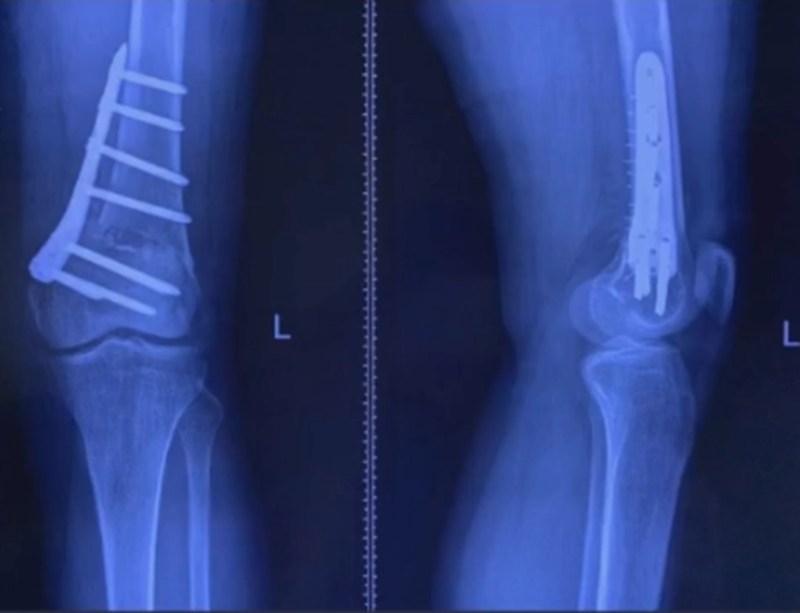

病例,X患者,女,双侧外翻膝,行双侧DFO。

术后6周摔伤,一侧出现膝内翻。

影像学检查显示左侧出现合页断裂。

进行翻修,术前力线显示内翻。

术中发现螺钉松动,截骨端出现坎插迹象。

近端螺钉松开,调整力线,重新固定后,在外侧加小钢板抗旋。

术后10周复查,力线较好。